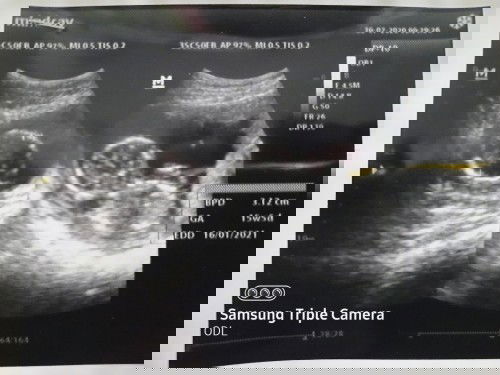

Bun adakah yg pernah keluar flek coklat? Aku Sudah USG 2x, ke bidan 1x, ke pukesmas 1x katanya gak papa dan disuruh bedrest total, dikasih obat penguat juga. Tapi sampai sekarang usia kandungan 19 week kadang2 masih keluar flek dikit di tissue. Udah positif thingking gak papa sesuai kata dokter tp kadang worry juga, adakah yg punya kasus sama? #bantusharing #seriusnanya